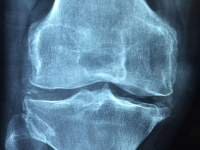

Subcategoría: Fisioterapia